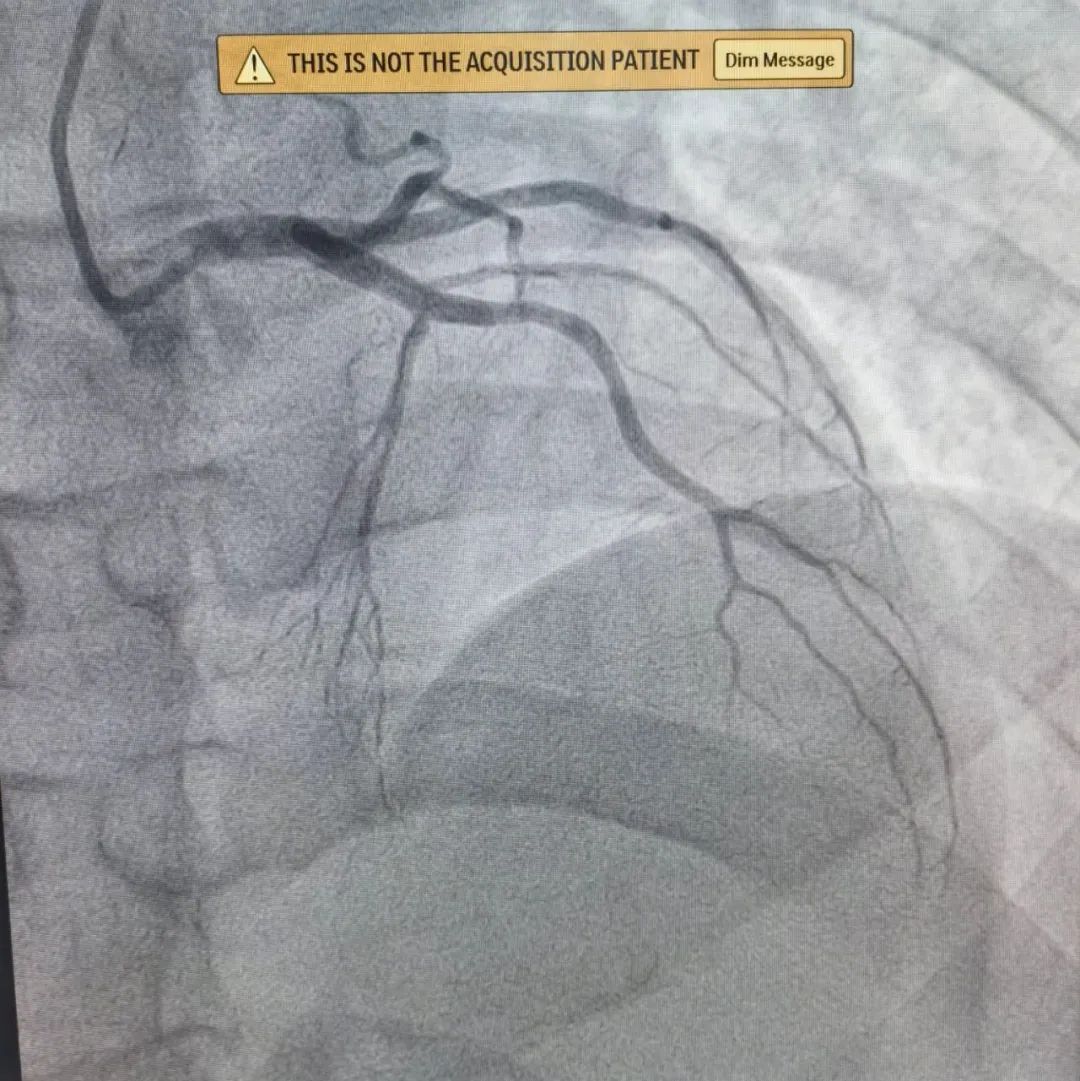

这位患者是位90后,因突发胸闷持续20余小时才来医院治疗,考虑到小伙子胸痛反复,无法缓解,病情危急,九龙湖院区心内科团队立即查找原因,原来小伙子最重要的一支心脏血管:“前降支”急性闭塞且血栓负荷重。于是,球囊扩张、血管内溶栓、支架植入......紧张又有序地手术操作结束后,小伙子闭塞的血管终于打通,胸痛症状也得到了明显缓解。

可是,张叔叔明明年纪不大,为什么一个呼吸道感染就会导致心衰这么危险的疾病呢?原来,张叔叔的心脏血管“前降支”出现了慢性闭塞。于是,心内科手术团队在血管内超声指导下精准植入2枚支架,使张叔叔的前降支血流恢复畅通。手术后,张叔叔的胸闷症状明显缓解,运动耐力也明显恢复,射血分数也由术前的42%显著回升到50%。